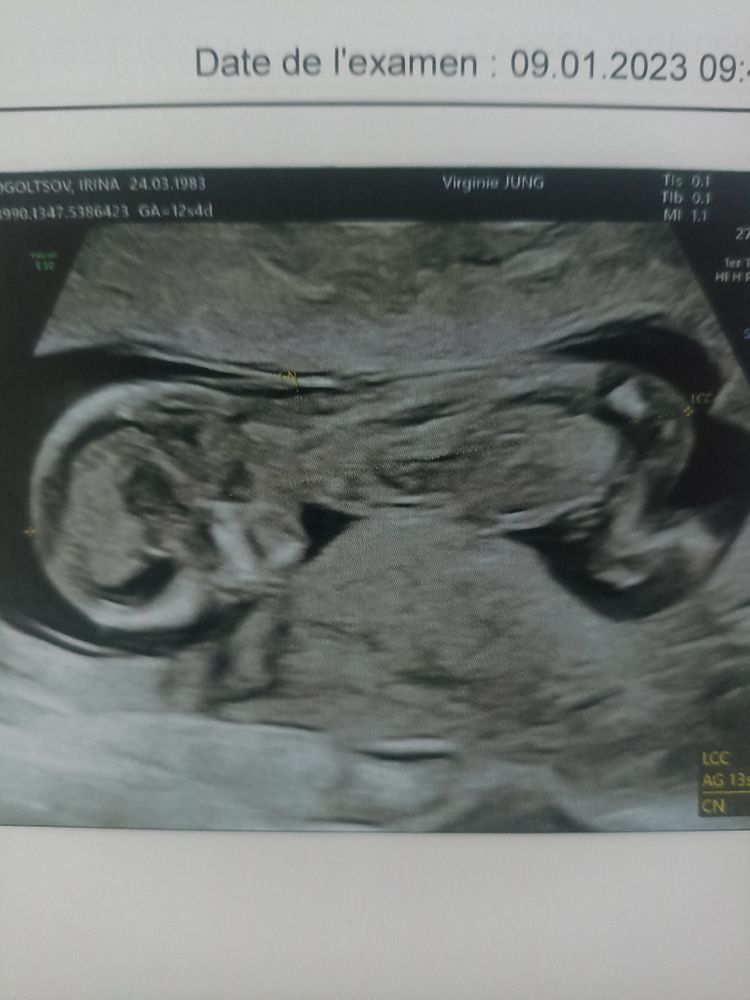

Первый скрининг 13 недель

Спешу поделиться, что сегодня утром была на УЗИ, очень сильно ждала, что скажут, что с нашей малюткой всё хорошо, но .... Врач предупредила, что в силу возраста и других причин (а я уже не молода и воротникового пространства 2.2мм, норма до 3мм, происхождения не французского, а яя славянского) скорее всего будут высокие риски и меня отправят на Нипт. По УЗИ усе идеально, но скрининг - это скорее статистический расчёт пороков, а Нипт это непосредственно кровь конкретной мамы и ребенка. Сдадим, куда денемся, иак делала с Максимом, а с Данькой вообще амниоцентез делали . Тем более всю стоимость анализа оплачивает медстраховка.

Пол ребенка не увидели, сначала спинкой, потом ножки скрещены были, но врач сказала, что догадывается кто. Следующий раз посмотрим снова.

Ну кто у нас хорошо разбирается в снимках, предположите пожалуйста, хотя я ни бугорка не нашла, ни мошонки, ни хвостика.